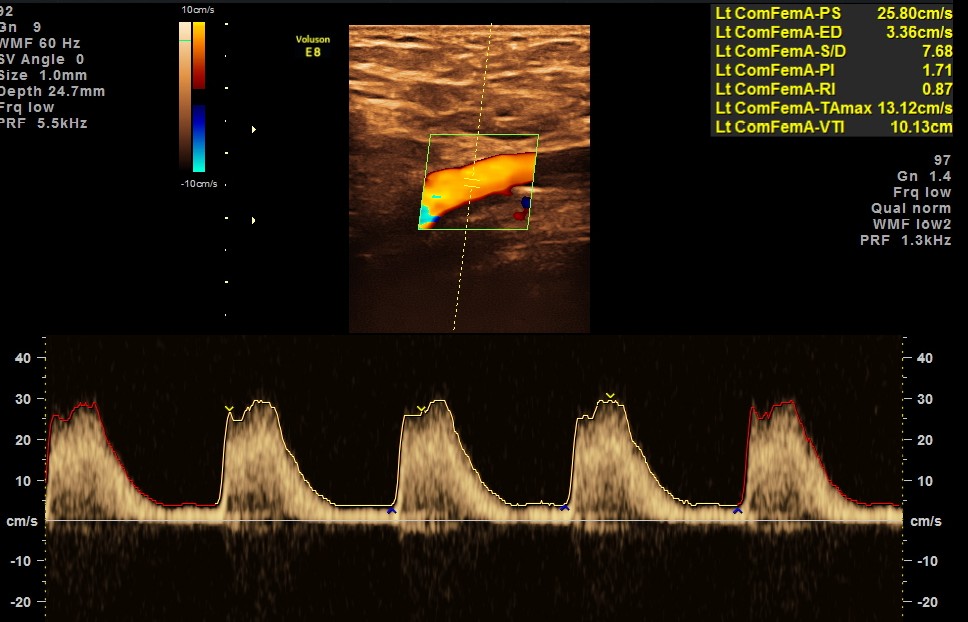

BOTH DORSALIS PEDIS ARTERIES SHOW LOSS OF ARTERIAL TONE AND MONOPHASIC FLOW.

BOTH COMMON ILIAC ARTERIES AND EXTERNAL ILIAC ARTERIES SHOWED TRIPHASIC FLOW.

EXTENSIVE ATHEROSCLEROTIC OBSTRUCTIVE DISEASE OF THE LOWER LIMB ARTERIES WAS SEEN WITH THE CHANGES IN THE RIGHT COMMON FEMORAL ARTERY BEING MORE THAN THE LEFT CFA.